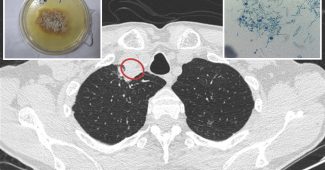

的现成的心脏补丁设计的团队首先decellularizing猪心脏组织,然后变成一个脚手架矩阵作为的主要结构的目的。此外,人造心脏基质细胞含有修复因素从实际获得的心脏基质细胞被添加到矩阵从而创建一个完整的解决方案,提供所有的治疗通常分泌细胞,但在完全人工的方式。

团队声称,基于实验,冰冻的补丁以及新鲜的工作,他们能够见证增加50%的心脏功能在老鼠模型中心脏病发作和疤痕减少30%的伤害。Cheng说,这个补丁可以冻结和安全存储至少30天,因为没有活细胞,它不会引起病人的免疫系统拒绝它。这是一个真正的第一步治疗心脏补丁现成的解决方案。